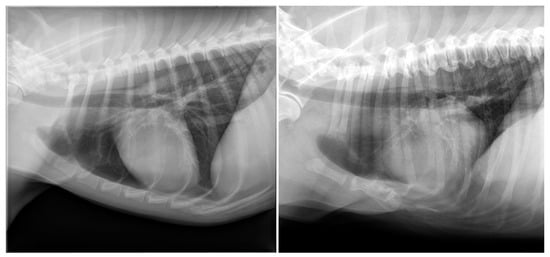

| Degeneration (n = 98) | New bone formation (n = 98); collapse (n = 13); vacuum phenomenon (n = 13); sclerosis (n = 9); dislocation (n = 5) | Labrador Retriever (16/62); mixed (13/145); Boxer (7/13); Flatcoated Retriever (7/15); Cavalier King Charles Spaniel (5/11); German Shepherd (5/21); Bernese Mountain Dog (4/26); Belgian Shepherd (3/8); Dachshund (3/19); English Cocker Spaniel (3/13); American Bulldog (2/6); Drentsche Patrijshond (2/6); Golden Retriever (2/23); Irish Setter (2/3); Labradoodle (2/22); Welsh Springer Spaniel (2/3); White Swiss Shepherd Dog (2/14); Anatolian Shepherd Dog (1/1); Border Collie (1/10); Border Terrier (1/4); Bouvier des Flandres (1/2); Chow Chow (1/3); English Springer Spaniel (1/4); Frisian Water Dog (1/2); Hovawart (1/2); Irish Wolfhound (1/2); Jack Russell Terrier (1/15); Kooikerhondje (1/5); Newfoundland (1/5); Dobermann (1/2); Rottweiler (1/10); Spanish Water Dog (1/3); Stabyhoun (1/12); West Highland White Terrier (1/3); Wirehaired Pointing Griffon (1/1) |